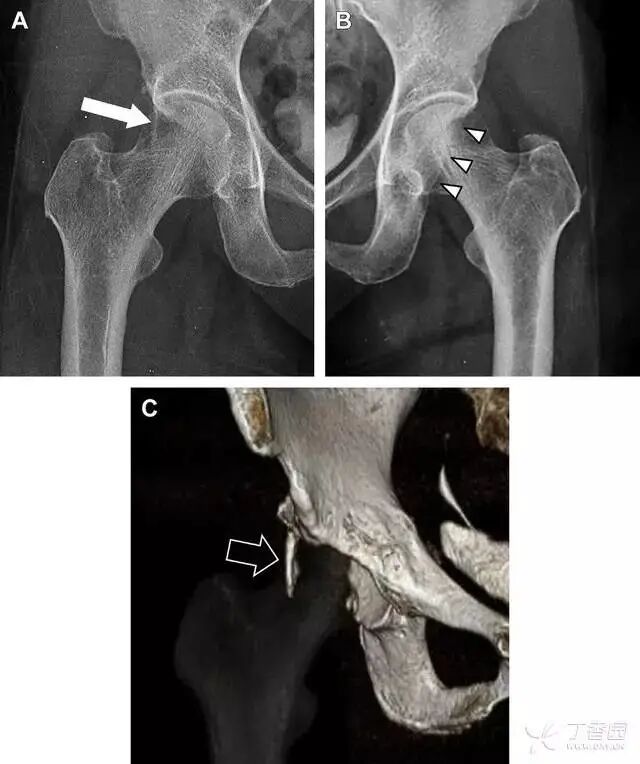

01髋臼骨折

髋臼骨折最常见的类型是髋臼后壁骨折,几乎占髋关节骨折的 1/4,且常常合并髋关节后脱位。由于骨性结构重叠,可能肉眼看上去觉得非常轻微的骨折,事实却并非如此。髋臼后缘中断常常是髋臼后壁骨折的一个特征(图 2)。

图 2 为髋臼后壁骨折伴髋关节脱位患者。A 右侧髋关节 X 线片示股骨头后方可见一骨折线(箭头),髋臼后缘中断。B 左侧髋关节 X 片对照可见髋臼后缘连续(箭头)。C  CT 三维重建图像示髋臼后壁缺损,可见旋转、移位的骨折块(箭头)